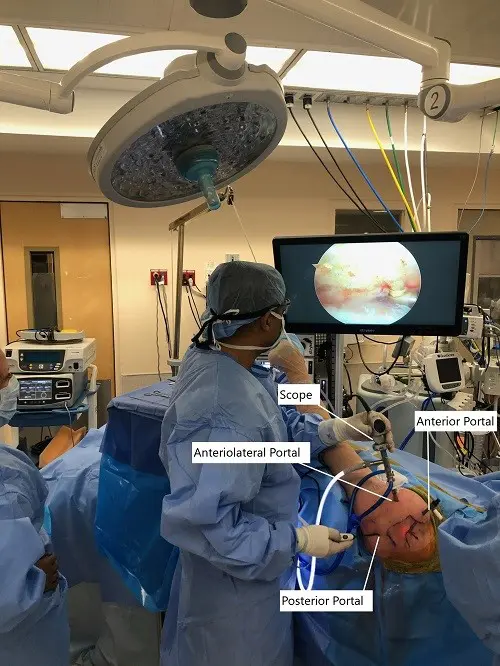

Intraoperative picture of arthroscopic shoulder surgery set up.

DESCRIPTION OF PROCEDURE: The patient was taken to the operating room where she was placed on a well-padded operating table. General anesthesia was induced. A supraclavicular block was given preoperatively. The patient was turned into the right lateral position with the left shoulder up. He was held in an excellent position in the beanbag. The axillary roll was used to pad the axilla. All the bony prominences were well padded.

The left upper extremity was prepped and draped aseptically in the usual fashion. Preoperative antibiotics were given. A posterolateral entry portal was made. The scope was entered. Examination of the glenohumeral joint showed extensive synovitis, degenerative arthritis of the glenohumeral joint more on the humeral head, absence of biceps, and the rotator cuff tear in the region of the supraspinatus and in infraspinatus.

An anterior entry portal was made and shaver was introduced and debridement of the synovitis was performed. Chondroplasty of the humeral head, as well as the glenoid, was also performed. The scope was entered from the anterior portal and findings were re-confirmed and debridement was completed.

The scope was entered in the subacromial space. The tear was found in the supra and infraspinatus region. Debridement was done and the bursa was removed. There was an acromial spur anteriorly. The spur was removed by the use of electrocautery followed by burr.

Acromioplasty was performed by removing the anterolateral acromial spur and as well as the inferior surface of anterior 2/3rd of the acromion. A decision was made to repair the rotator cuff. An accessory lateral portal was made. The footprint for the rotator cuff was debrided using a burr exposing the subcortical bone.